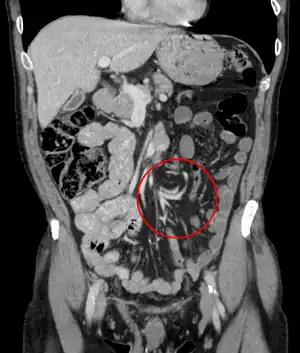

Volvulus with gangrene of the sigmoid

Sigmoid

Treatment for sigmoid volvulus may include sigmoidoscopy. If the mucosa of the sigmoid looks normal and pink, a rectal tube for decompression may be placed, and any fluid, electrolyte, cardiac, kidney or pulmonary abnormalities should be corrected. The affected person should then be taken to the operating room for surgical repair. If surgery is not performed, there is a high rate of recurrence.

For people with signs of sepsis or an abdominal catastrophe, immediate surgery and resection is advised.